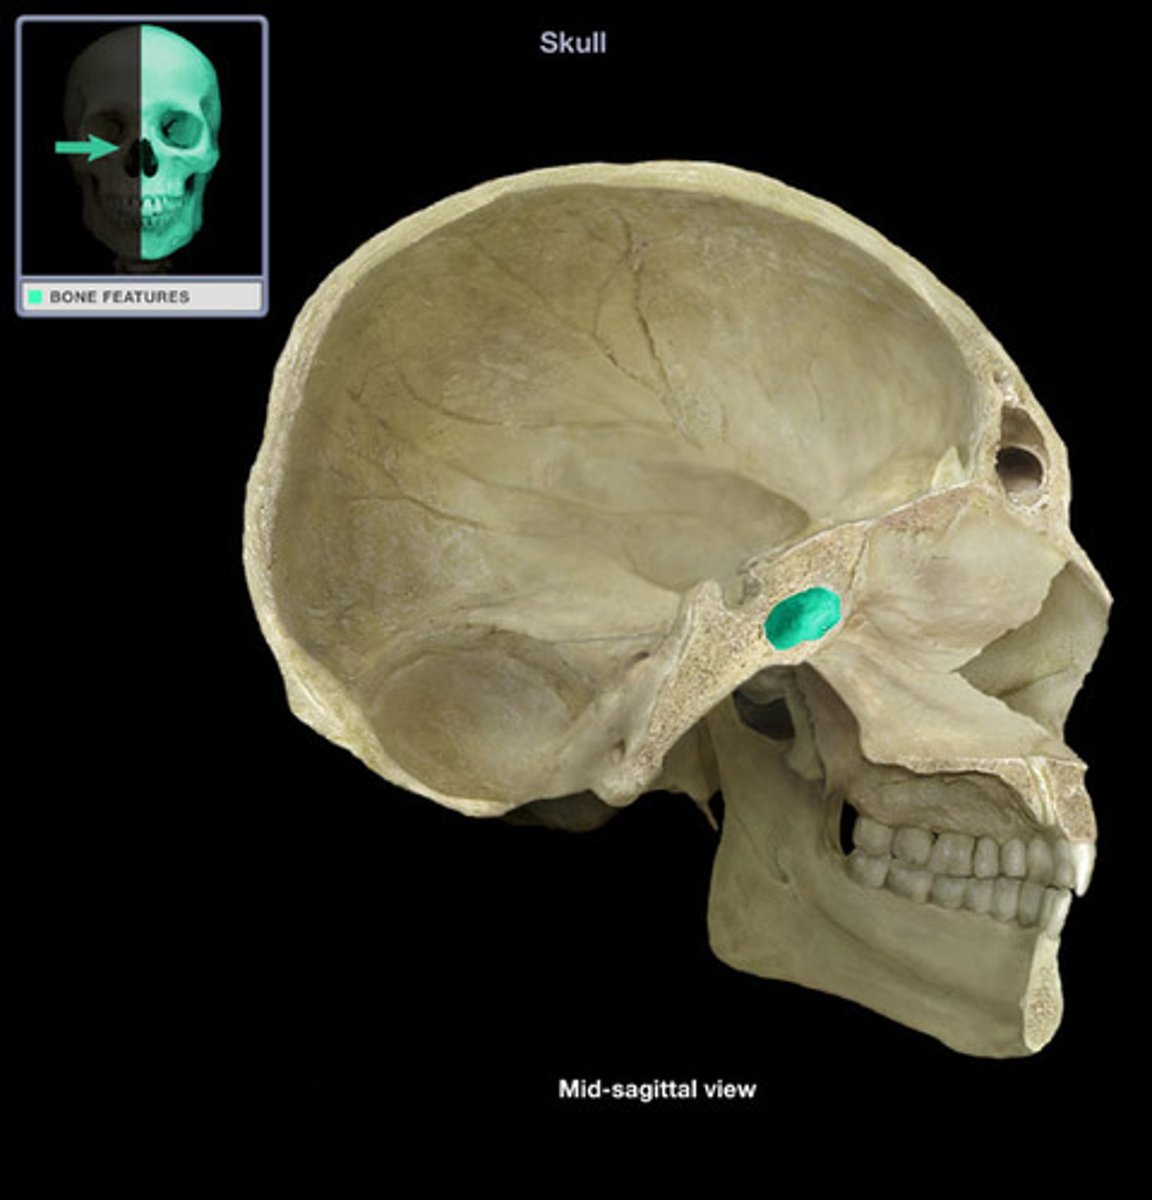

pterion

Junction of frontal, parietal, sphenoid, and temporal bones. Structural vulnerability as it is thin and middle meningeal artery is just deep, so hard head blow can result in subdural hematoma